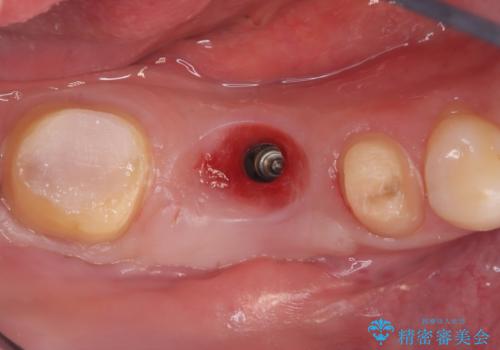

インプラント周囲の歯肉が薄かったため、**FGG(遊離歯肉移植術)**を行い、長期安定に不可欠な「角化歯肉」を確保する。

FGG(遊離歯肉移植術)の実施: インプラントを長持ちさせるためには、周囲に硬く動かない「角化歯肉」が必要です。患者様の上あごから丈夫な歯肉を移植するFGGを行うことで、インプラント周囲に十分な厚みと幅のある角化歯肉を形成しました。